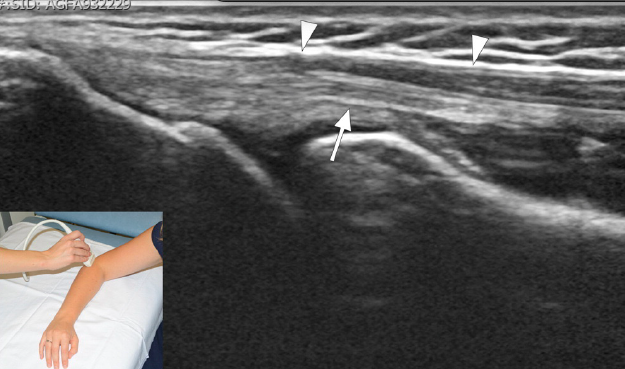

¿Cómo se ve el codo de tenista/golfista en US?

A

• Muy útil

• Tendón engrosado, hipoecogénico

• Rotura

How well did you know this?